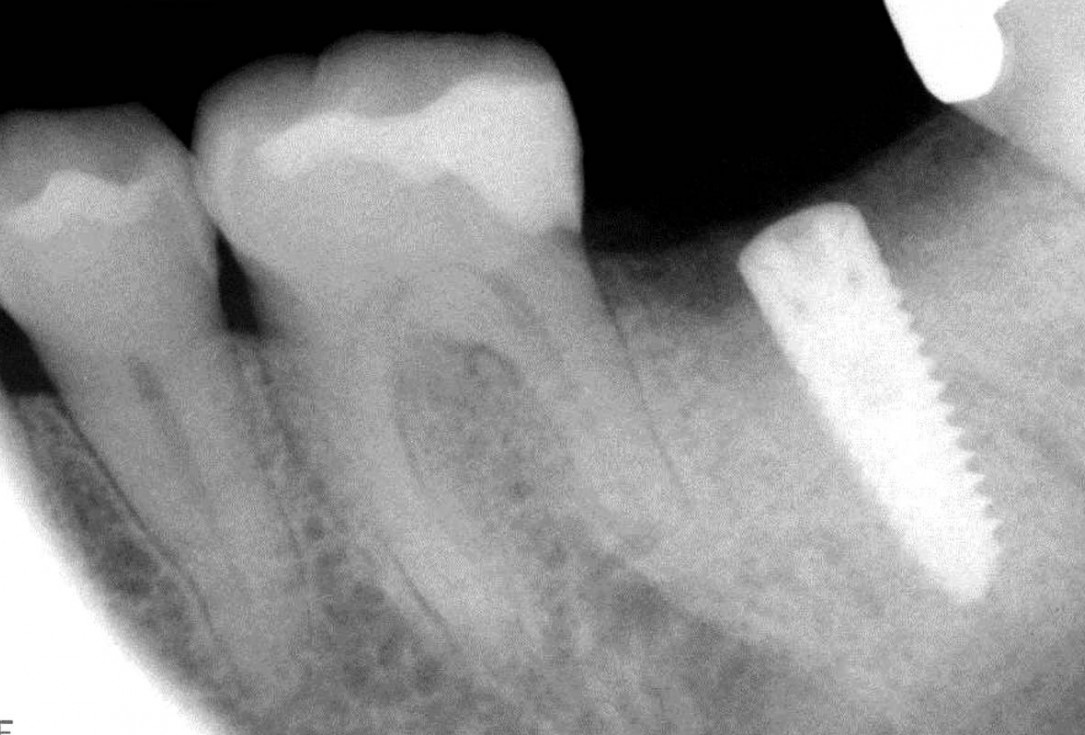

botiss cerabone® & collagen fleece for immediate implantation - Clinical case by Dr. D. Jelušić

Clinical situation before extraction and implantation